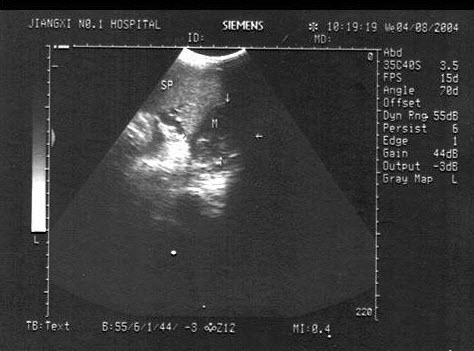

24、单项选择题

女性,25岁,停经35周。产前超声检查,图像显示的是胎儿的()

A.脊柱

B.肢体

C.颜面部

D.胸腔

E.胎头

25、单项选择题

图示4所指部位()

A.脾静脉

B.腹主动脉

C.肠系膜上动脉

D.胰头

E.下腔静脉